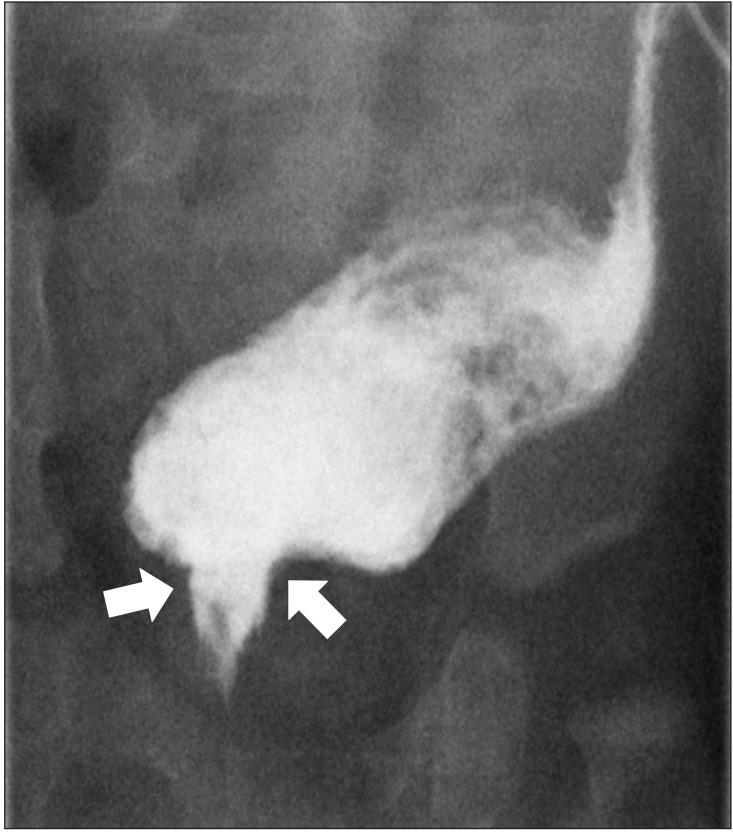

The Currarino triad is a unique complex of congenital caudal anomalies, including anorectal malformation, sacral bony defect and presacral mass. This triad may be associated with Müllerian duct anomalies, such as duplication of the vagina and uterus. Each of these diseases has a familial tendency and sometimes coexist within families. But, when coexisting in familial cases, nearly all reported cases revealed mutations of the motor neuron and pancreas homeobox 1 (MNX1) gene. Familial cases of Currarino triad combined with Müllerian duct anomaly without MNX1 gene mutation are very rare. Here we report cases of mother and daughter, who had Currarino triad and Müllerian duct anomaly without MNX1 gene mutation, along with a brief literature review.